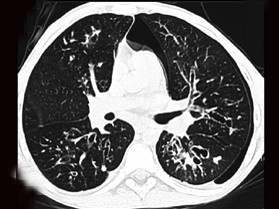

男,38岁,咳嗽、咳痰、咯血,结核菌素实验(-),结合CT图像,最可能的诊断是 ( ) WXJ-01891.jpg WXJ-01892.jpg

• D.支气管扩张